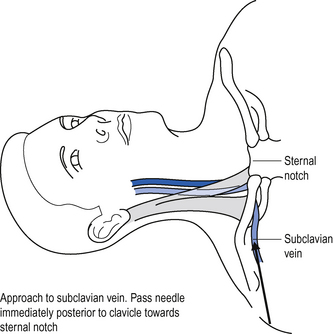

Subclavian vein

The subclavian vein is a continuation of the axillary vein. It runs from the apex of the axilla behind the posterior border of the clavicle and across the first rib to join the internal jugular vein, forming the brachiocephalic vein behind the sternoclavicular joint. See Fig. 15.2.

Position the patient supine (some people advocate placing a sandbag between the patient’s shoulder blades, which allows the shoulders to drop back out of the way).

Position the patient supine (some people advocate placing a sandbag between the patient’s shoulder blades, which allows the shoulders to drop back out of the way). Introduce the needle just beneath the clavicle at this point, and aim towards the clavicle until contact with bone is made.

Introduce the needle just beneath the clavicle at this point, and aim towards the clavicle until contact with bone is made. To locate the vein, redirect the needle closely behind the clavicle and towards the suprasternal notch.

To locate the vein, redirect the needle closely behind the clavicle and towards the suprasternal notch.Femoral vein